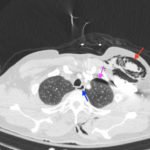

A 52-year-old male presented to the emergency room with left chest wall pain and upper back pain after falling from an estimated height of 24 feet, landing on his back. On physical exam, the patient had crepitus to left chest wall and back and was persistently hypotensive in the trauma bay.

Plain film anteroposterior (AP) radiography of the chest shows left-sided subcutaneous emphysema (red arrow) with overlapping muscle striations of the pectoralis major (green arrow). After chest tube placement (blue arrow), AP chest radiography shows persistent left-sided subcutaneous emphysema (red arrow). CT of the chest shows pneumomediastinum (blue arrow), left apical pneumothorax (pink arrow), and subcutaneous emphysema (red arrow) at the level of T2. At the level of T6, rib fractures can be visualized on the CT (yellow arrow). At the level of T8, left sided pneumothorax is also seen (pink arrow) as the absence of lung tissue on CT.

Injuries of the thorax account for 25% of all mortality in trauma patients, of which many are preventable deaths by simple interventions.1,2 One sign commonly seen in patients with chest trauma is subcutaneous emphysema. The presence of this underlying emphysema has been suggested to be a sign of injury to the respiratory tract, making it clinically significant.3,4 Specifically, subcutaneous emphysema has been shown to be a clinical predictor of occult pneumothorax, with an odds ratio of 5.47.3 Furthermore, these injuries to the respiratory tract (pneumothorax /hemothorax, pneumomediastinum, etc.) can lead to hemodynamic instability and respiratory failure.4-6

Treatment of these injuries consist of different measures. Subcutaneous emphysema does not usually require treatment and will reabsorb spontaneously.7 Pneumothorax and hemothorax are both treated with chest tube placement. In a hemothorax, however, if the tube evacuates more than 1,500 mL of blood immediately or more than 200 mL/hour, the patient should be taken to the operating room for surgical exploration of the chest.8 Therefore, complete investigation into the underlying cause of subcutaneous emphysema is essential in managing patients with chest trauma.

In this patient, given the findings of multiple bilateral rib fractures, bilateral hemothorax/pneumothorax and multiple spine fractures, bilateral chest tubes were placed which had immediate output. The patient was admitted to surgical intensive care unit for chest tube management, pulmonary hygiene and further management of his other injuries.